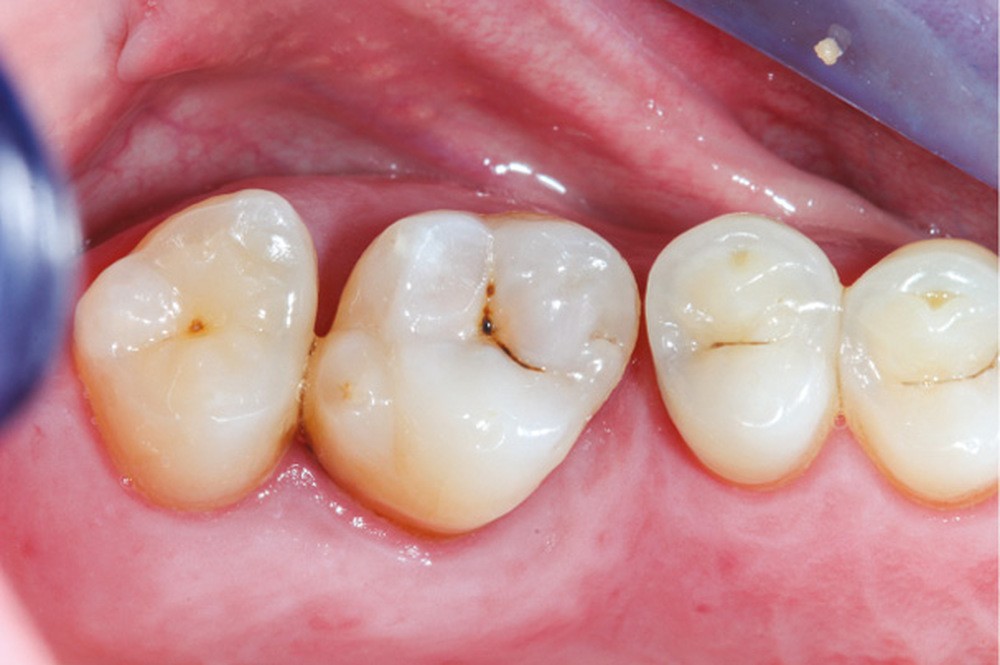

Cette version, quand elle se produit, modifie les espaces interdentaires et complique l’hygiène proximale des patients. Des caries peuvent alors se développer en interproximal sans que cela soit forcément visible à l’examen visuel (fig. 3 et 4). Les radios de type bite-wing (rétro-coronaires) prennent alors tout leur sens (fig. 5 et 6).

Des conséquences sur l’arcade antagoniste s’ajoutent à toutes les perturbations de l’arcade concernée. La dent antagoniste à l’édentement n’est plus calée et peut par conséquent s’égresser. Cette égression modifie les points de contact et les espaces interdentaires, pouvant conduire à des tassements alimentaires et des caries secondaires [18, 19].